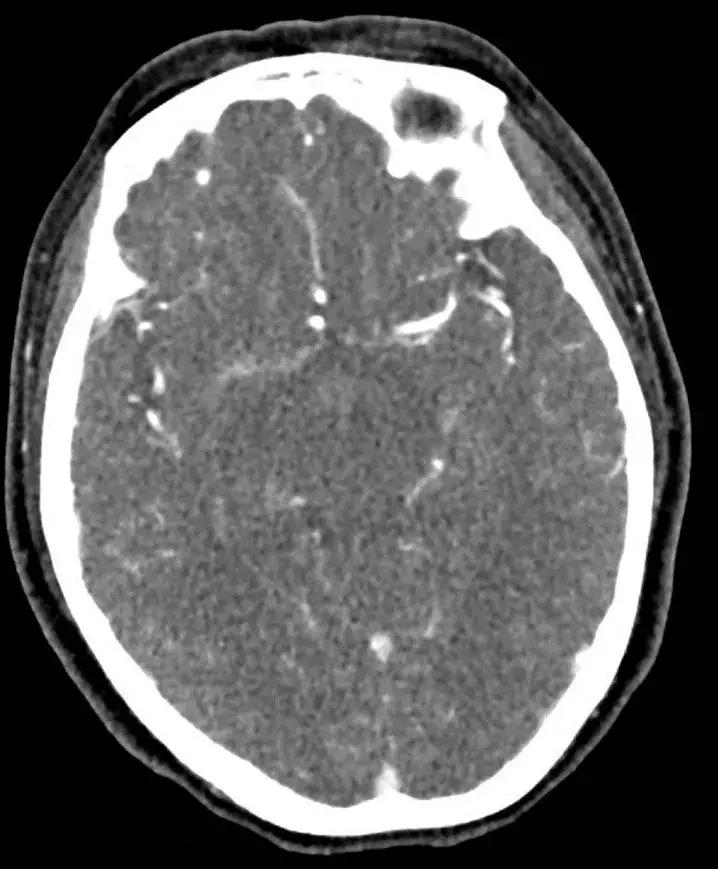

下丘脑见一类圆形异常信号灶,大小约1.6×1.4cm,T2WI呈等略高信号,T1WI呈等信号,DWI呈等信号,增强后明显异常强化,轻度压迫视交叉,FLAR见视交叉及双侧后方视束信号增高。

LCH颅内疾病影像表现主要包括:1. 颅面骨,颅底和鼻窦的病变:颅面骨受累最常表现为骨质破坏、肿瘤浸润和向颅内侵犯,受累最多的是颞骨(54%)、穹窿(47%)、眼眶(37%)和眶外面部骨骼(30%)。鼻窦和乳突受累最常见的表现是窦内变浑浊,呈液体或软组织信号,也可伴骨质破坏及强化。2. 颅内/轴外病变:1)脑膜病变:T1WI上等或低信号,T2WI上低信号,可有不同程度的强化,伴或不伴有骨质破坏;2)脉络丛病变:大小超过1/3三角区/平面、光整的钙化、类四叶草表现,后续随访中病灶增大;3)松果体病变:囊变、增大;4)下丘脑-垂体区病变:漏斗柄增粗>3mm伴强化,垂体后叶高信号的缺失,下丘脑肿块。3. 颅内/轴内病变:血管周围间隙和血管周围空间原本是几乎不可见的,LCH患者可在T2WI上可见扩大的间隙,有时会产生占位效应。脑干、脑桥主要是白质脑病样病变(弥漫或斑片状、通常对称,T2WI高信号,T1WI低信号,周围血管分布不清)。小脑白质增强:T2WI高信号,T1WI等信号或低信号,无占位效应。基底节区、小脑齿状核可出现异常信号,T1WI高信号或低信号,T2WI等信号,低信号或高信号。还可导致脑萎缩 。